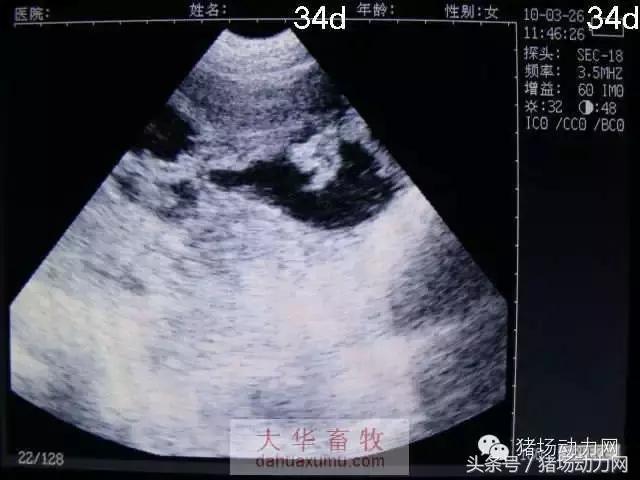

以下为怀孕母猪21天到90天之内的变化图:

34天